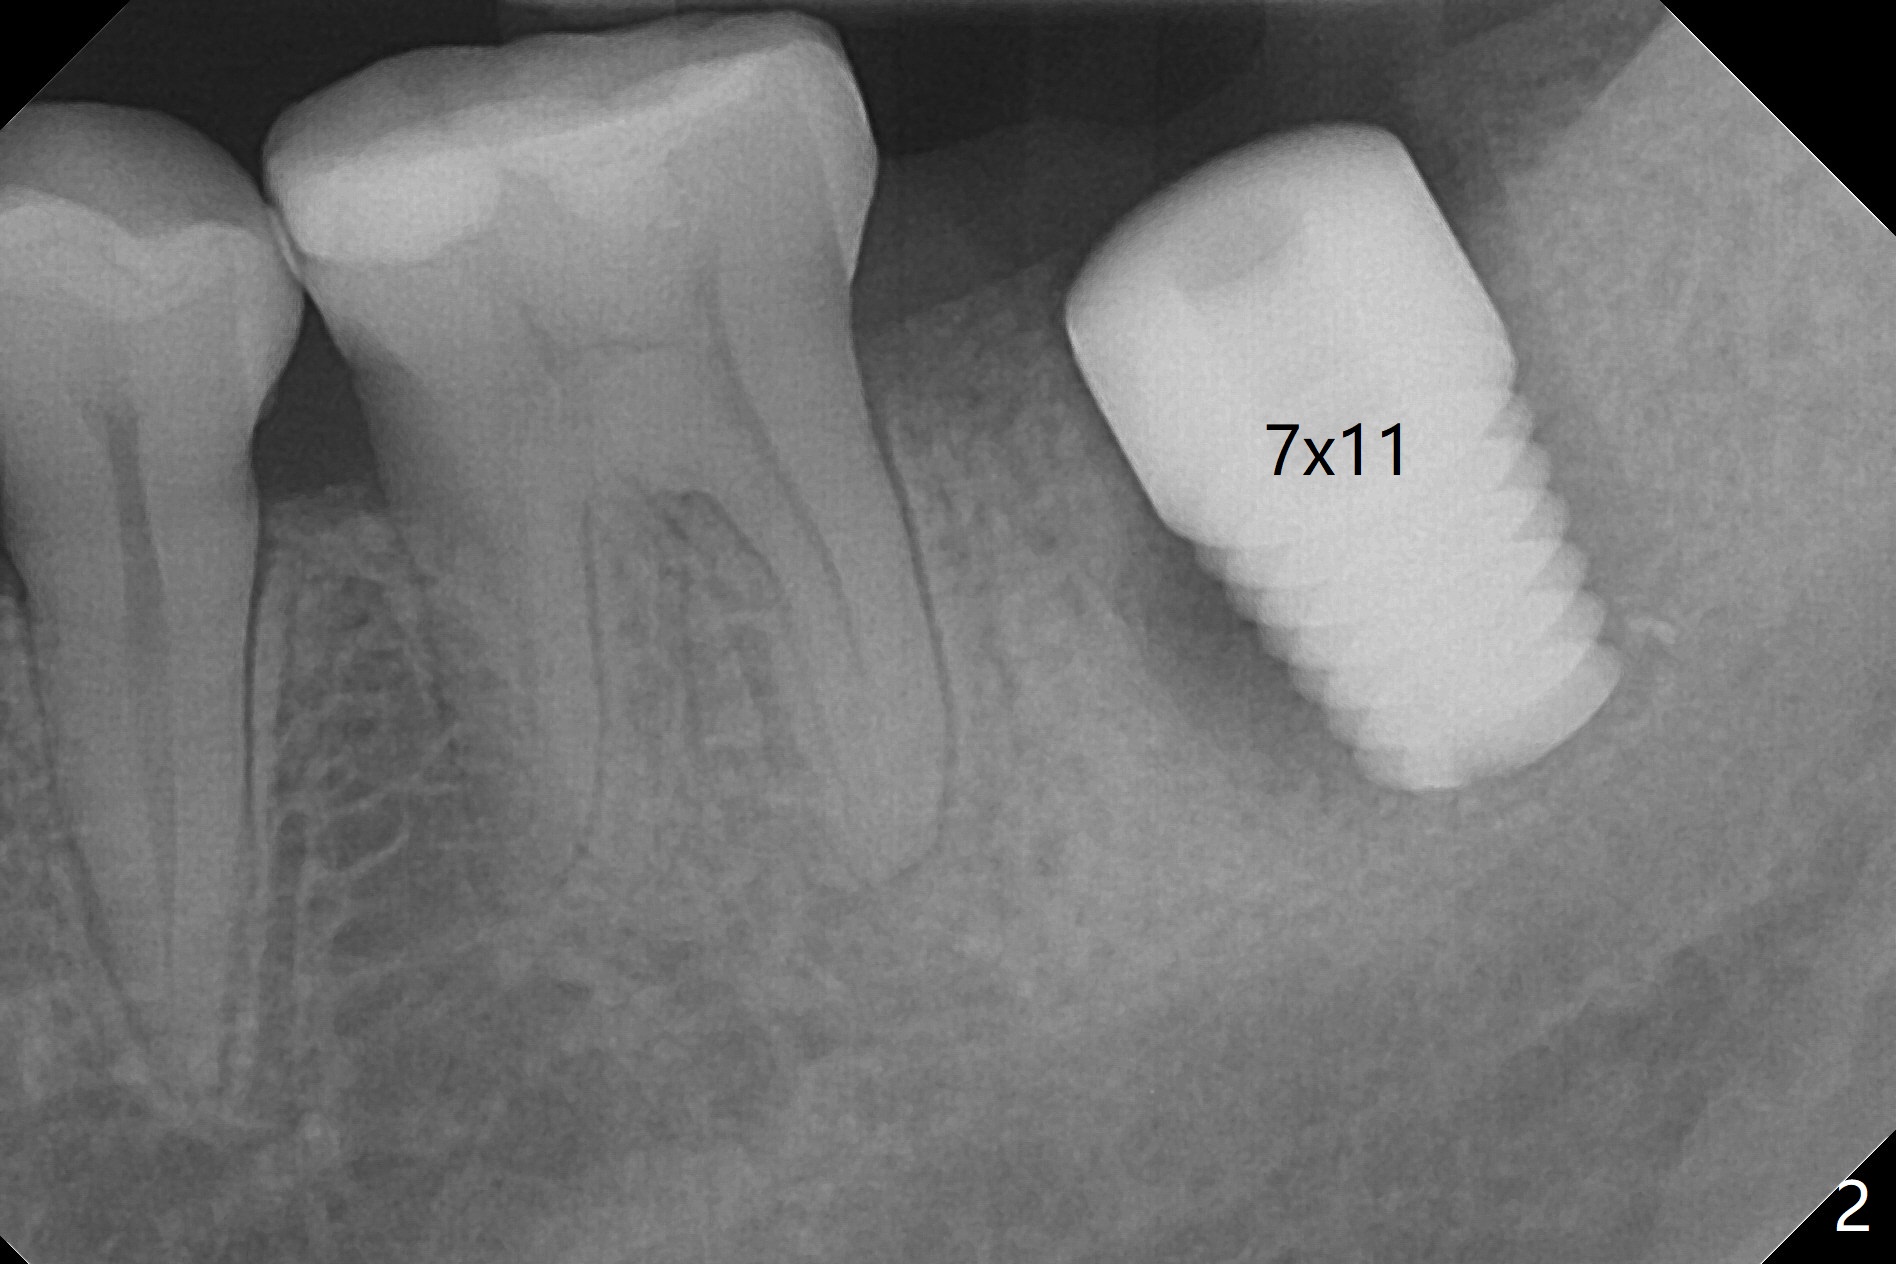

The patient with chronic buccal abscess at #31 is nervous. After extraction, a 7x11 mm tapered implant drops into the single socket, which is close to the Inferior Alveolar Canal (Fig.2). The bottom of the socket is sensitive to manipulation (explorer) after infiltration anesthesia. A 8x14 mm tapered tap is placed without binding, neither is a 8x14 mm cylindrical implant. The implant stability does not increase when Vera (.2-1.0 mm) or Vanilla (.5-1.0 mm) Graft is placed. Socket preservation is finished with Collagen plug and 6-month membrane (Fig.3,4).